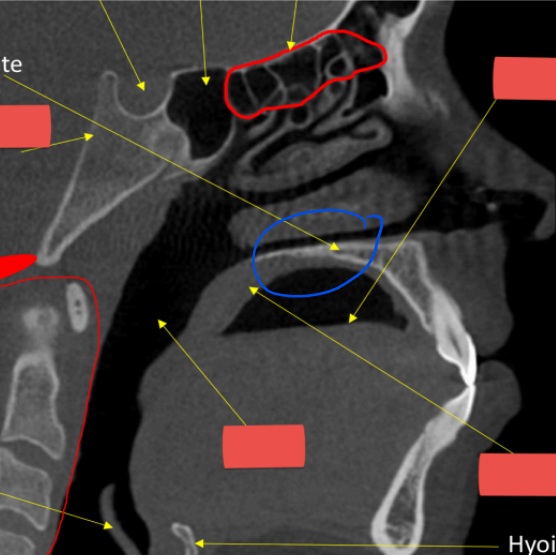

hyoid

hard palate

anterior nasal spine